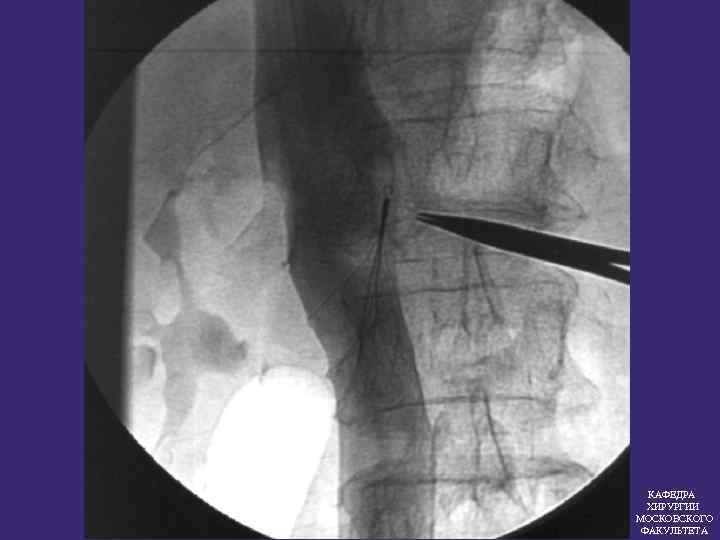

ПРОТИВОЭМБОЛИЧЕСКИЕ КАВАФИЛЬТРЫ Эффективность кава фильтров 97, 5% КАФЕДРА ХИРУРГИИ МОСКОВСКОГО ФАКУЛЬТЕТА

ПОКАЗАНИЯ К ИМПЛАНТАЦИИ КАВА-ФИЛЬТРА 1. Флотирующие тромбы в системе НПВ 2. Массивная ТЭЛА Повторные ТЭЛА без установленного источника 3. КАФЕДРА ХИРУРГИИ МОСКОВСКОГО ФАКУЛЬТЕТА